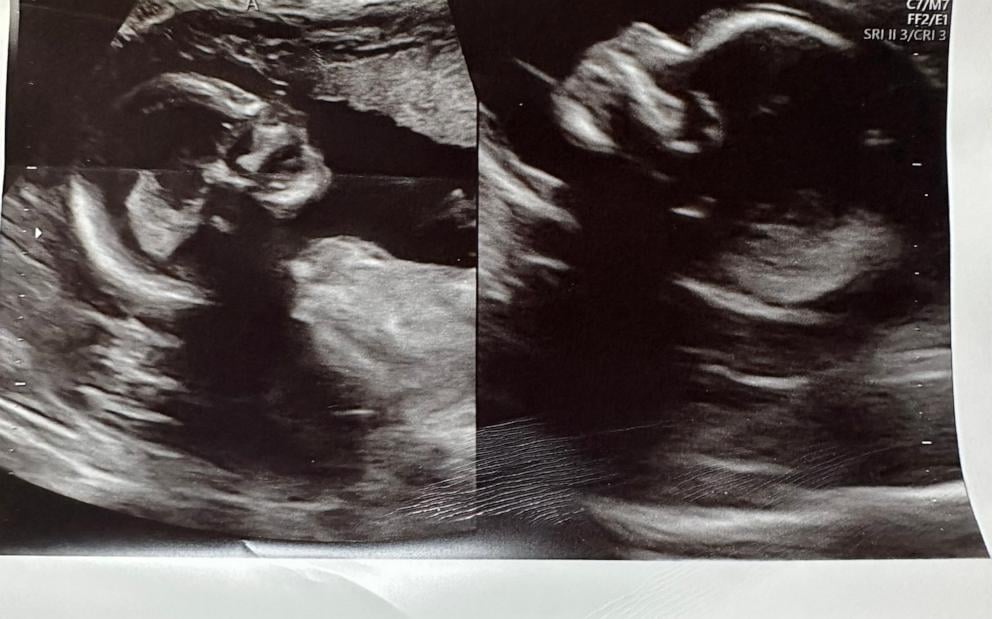

Kelsey dowiedziała się, że ma podwójną macicę w wieku 17 lat, ale w jej przypadku wada ta nie okazała się czynnikiem uniemożliwiającym urodzenie dziecka – ma już trójkę! Każda z poprzednich ciąż przebiegła bezproblemowo, a dzieci urodziły się zdrowe. Kiedy okazało się, że kobieta znowu jest w ciąży, ale tym razem z bliźniętami, było to szokiem – zarówno dla niej, jak i pielęgniarki, która przeprowadzała badanie USG. Kobieta przyjęła tę wiadomość śmiechem – po prostu nie mogła uwierzyć w to, co się wydarzyło.

Ciąża jest cały czas monitorowana, a dzieci rozwijają się prawidłowo – mają przyjść na świat w Boże Narodzenie. Dla wszystkich jest to zupełnie nowe doświadczenie, bo w medycynie nie opisano zbyt wielu podobnych przypadków. Nie ma eksperta, który wiedziałby, jak postępować z pacjentką z podwójną macicą i ciążą bliźniaczą.